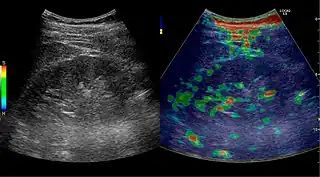

Complex cysts can have membranes dividing the fluid-filled center with internal echoes, calcifications or irregular thickened walls. The complex cyst can be further evaluated with Doppler US, and for Bosniak classification and follow-up of complex cysts, either contrast-enhanced ultrasound (CEUS) or contrast CT is used (Figure 6). The Bosniak classification is divided into four groups going from I, corresponding to a simple cyst, to IV, corresponding to a cyst with solid parts and an 85–100% risk of malignancy.[1] In polycystic kidney disease, multiple cysts of varying size in close contact with each other are seen filling virtually the entire renal region. In advanced stages of this disease, the kidneys are enlarged with a lack of corticomedullary differentiation (Figure 7).[1]

Figure 6. Complex cyst with thickened walls and membranes in the lower pole of an adult kidney. Measurements of kidney length and the complex cyst on the US image are illustrated by '+' and dashed lines.[1]